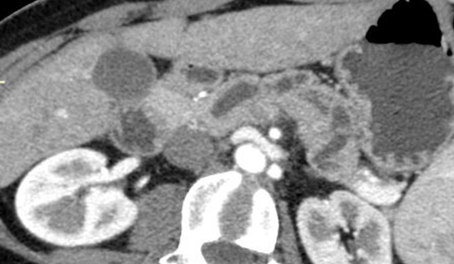

Lesione non visibile all’imaging. Dilatazione del dotto pancreatico principale all’esame TC con stop in regione istmica in assenza di lesioni focali.

image